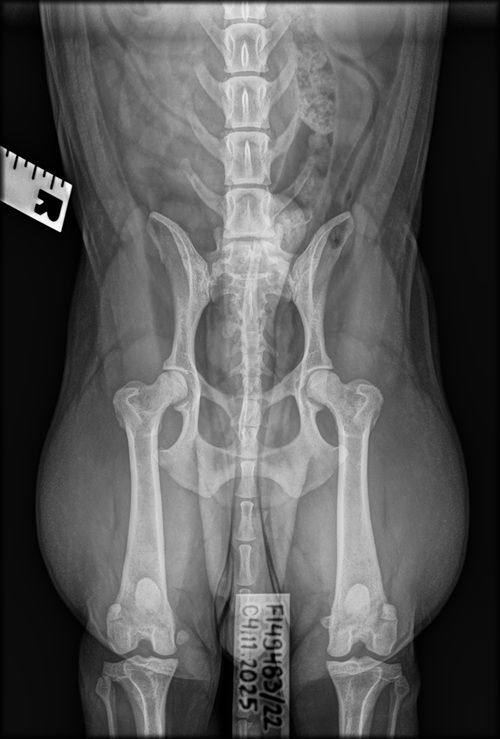

Welmun luustokuvat 4.11.2025

Walesipoika Welmu (Vicway Sweeney Todd) pääsi marraskuun alussa uuteen eläinsairaala Sacrumiin virallisiin luustokuviin ortopedi Emmi Syrjäselle. Tarkoitus oli kuvata lonkat, kyynärät ja selkä sekä tutkia polvet virallisesti (aiempi tutkimus keväällä 2023 jäi epäviralliseksi koiran nuoren iän takia), mutta kuvasivat eläinsairaalassa vahingossa olatkin, joten lisättiin nekin sitten lennossa pakettiin.

Kaikki on kuvien perusteella ihan hyvin Welmun ruodossa, ainoa selkeä havainto oli viimeisessä lannenikamassa, joka muistuttaa niin asennoltaan kuin malliltaankin ristinikamaa. Oikean lonkan ortopedi arvioi myös vasempaa löysemmäksi (ja ero näkyy maallikollekin kuvassa), mutta lonkkamaljat ovat syvät ja lonkat muutenkin siistit, ja B:nä tulivatkin molemmat takaisin Kennelliitolta. Kyynärät, olat ja selkä muilta osin puhtaat, ja polvet kunnossa.

- Vicway Sweeney Todd “Welmu”: lonkat B/B, kyynärät 0/0, selkä LTV2+VA0+SP0, olat terveet, polvet 0/0